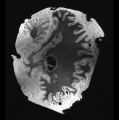

In neuroimaging, MRI tissue properties characterize underlying neurobiology, provide quantitative biomarkers for neurological disease detection and analysis, and can be used to synthesize arbitrary MRI contrasts. Estimating tissue properties from a single scan session using a protocol available on all clinical scanners promises to reduce scan time and cost, enable quantitative analysis in routine clinical scans and provide scan-independent biomarkers of disease. However, existing tissue properties estimation methods - most often $\mathbf{T_1}$ relaxation, $\mathbf{T_2^*}$ relaxation, and proton density ($\mathbf{PD}$) - require data from multiple scan sessions and cannot estimate all properties from a single clinically available MRI protocol such as the multiecho MRI scan. In addition, the widespread use of non-standard acquisition parameters across clinical imaging sites require estimation methods that can generalize across varying scanner parameters. However, existing learning methods are acquisition protocol specific and cannot estimate from heterogenous clinical data from different imaging sites. In this work we propose an unsupervised deep-learning strategy that employs MRI physics to estimate all three tissue properties from a single multiecho MRI scan session, and generalizes across varying acquisition parameters. The proposed strategy optimizes accurate synthesis of new MRI contrasts from estimated latent tissue properties, enabling unsupervised training, we also employ random acquisition parameters during training to achieve acquisition generalization. We provide the first demonstration of estimating all tissue properties from a single multiecho scan session. We demonstrate improved accuracy and generalizability for tissue property estimation and MRI synthesis.